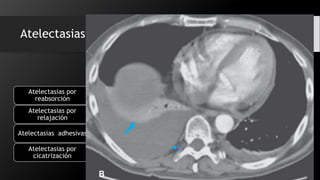

Atelectasias La palabra atelectasia se utiliza de manera

especifica para denotar disminución de gas en el pulmón

asociada con disminución del volumen pulmonar

que no implica por necesidad un incremento en la radioopacidad.

•Ocurren cuando la comunicación entre el alveolo y la tráquea esta obstruida.Atelectasias por

reabsorción

Atelectasias por

relajación

•Es una atelectasia con vías aéreas permeables, que probablemente está relacionada con

problemas del surfactanteAtelectasias adhesivas

•Es una pérdida de volumen que acompaña a la fibrosis pulmonar y que es generalmente

secundaria a lesiones inflamatorias crónicas

cicatrización

Atelectasias La palabraatelectasia se utiliza de manera especifica para denotar disminución de gas en el pulmón asociada con disminución del volumen pulmonar que no implica por necesidad un incremento en la radioopacidad. •Ocurren cuando la comunicación entre el alveolo y la tráquea esta obstruida.Atelectasias por reabsorción •Es la pérdida de volumen que acompaña a grandes procesos que ocupan espacio en el tórax Atelectasias por relajación •Es una atelectasia con vías aéreas permeables, que probablemente está relacionada con problemas del surfactanteAtelectasias adhesivas •Es una pérdida de volumen que acompaña a la fibrosis pulmonar y que es generalmente secundaria a lesiones inflamatorias crónicas Atelectasias por cicatrización